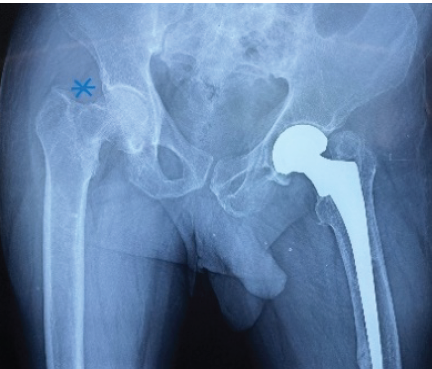

A 60-year-old male patient presented with complaints of right hip pain and inability to bear weight on his right lower limb for 10 days, with no history of recent trauma. The patient also had a history of neck of femur fracture in his left hip due to a traumatic cause, which was treated with uncemented hemiarthroplasty (elsewhere) 4 years ago. Clinical examination revealed shortening of the right lower limb, groin tenderness, and absent active SLR with no distal neurovascular deficits. X-ray of the pelvis with both hips revealed a pathological fracture in the right neck of the femur with a lytic lesion at the basicervical region of the neck of the femur (Fig. 1).

Figure 1: Pre-operative radiograph revealing an osteolytic lesion in the right neck of the femur (blue asterisk) and left hip bipolar implant in situ.

Figure 3: Post-operative radiograph showing cemented total hip replacement (right hip).